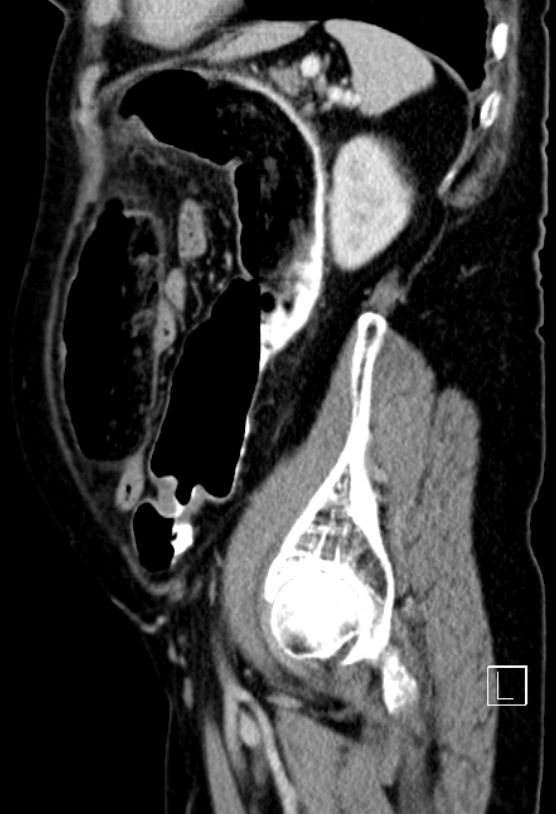

| Klinik | 72jähriger Mann mit kaffeesatzähnlichem, rötlichen Urin und 15kg Gewichtsabnahme. Stuhldurchmesser seit 4 Monaten vermindert.![]() |

![]() |